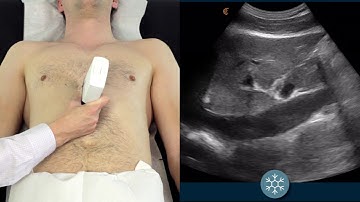

IVC for Fluid Responsiveness